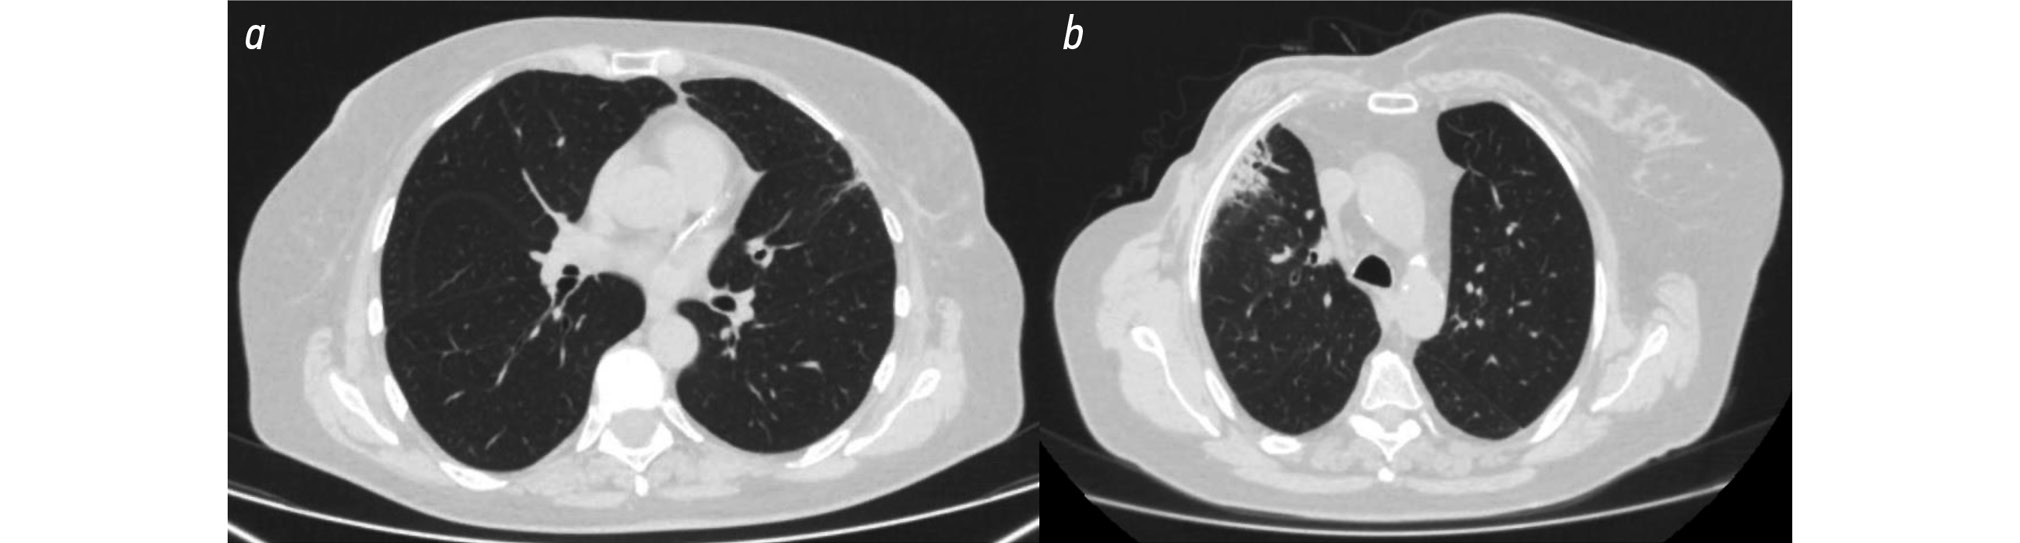

Group 1 consisted of 13 patients who exhibited minimal postradiation changes (Fig. 1a), while Group 2 included 23 patients with severe postradiation pneumofibrosis (Fig. 1b).

Fig. 1. Chest computed tomography at 6 months postradiation therapy: a, minimal postradiation changes in the left lung; b, severe postradiation pneumofibrosis in the right lung.